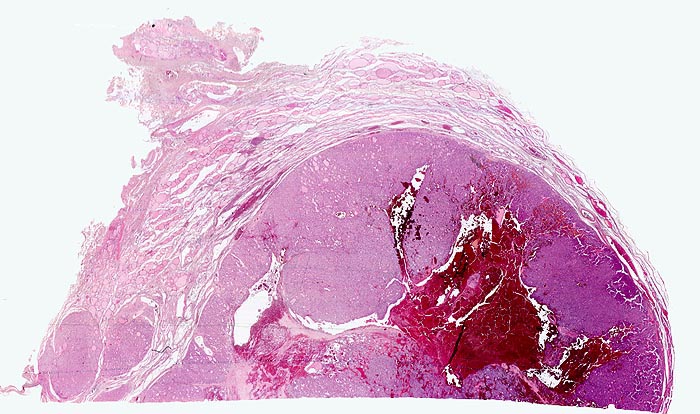

PathoPic – image database / PathoPic ID 4835 - autonomes Adenom

autonomes Adenom

benigner Tumor

Schilddrüse

Scharf begrenzter basophiler Knoten mit angedeuteter Kapsel und zentraler frischer Einblutung. Der Knoten komprimiert das angrenzende Schilddrüsenparenchym. Innerhalb des Knotens sind gar keine oder nur sehr kleine Follikellumina erkennbar. Zwei kleine Knoten mit ähnlicher Morphologie liegen unmittelbar neben dem grossen Knoten.

Die 52-jährige Patientin gibt an, in letzter Zeit vermehrt Herzpalpationen verspürt zu haben. Zusätzlich sei ihr aufgefallen, dass sie nervöser geworden sei, teilweise sogar aggressiv. Sie stellte eine ungewollte Gewichtsabnahme fest.

In der insgesamt eher verkleinerten Schilddrüse ist ein solitärer nicht schmerzhafter Knoten palpabel. Sonographisch kann der klinische Befund bestätigt werden. Die Szintigraphie ergibt eine vermehrte Speicherung von 123-Iodid im Knoten. Freise T3 und T4 sind erhöht, das TSH ist erniedrigt.